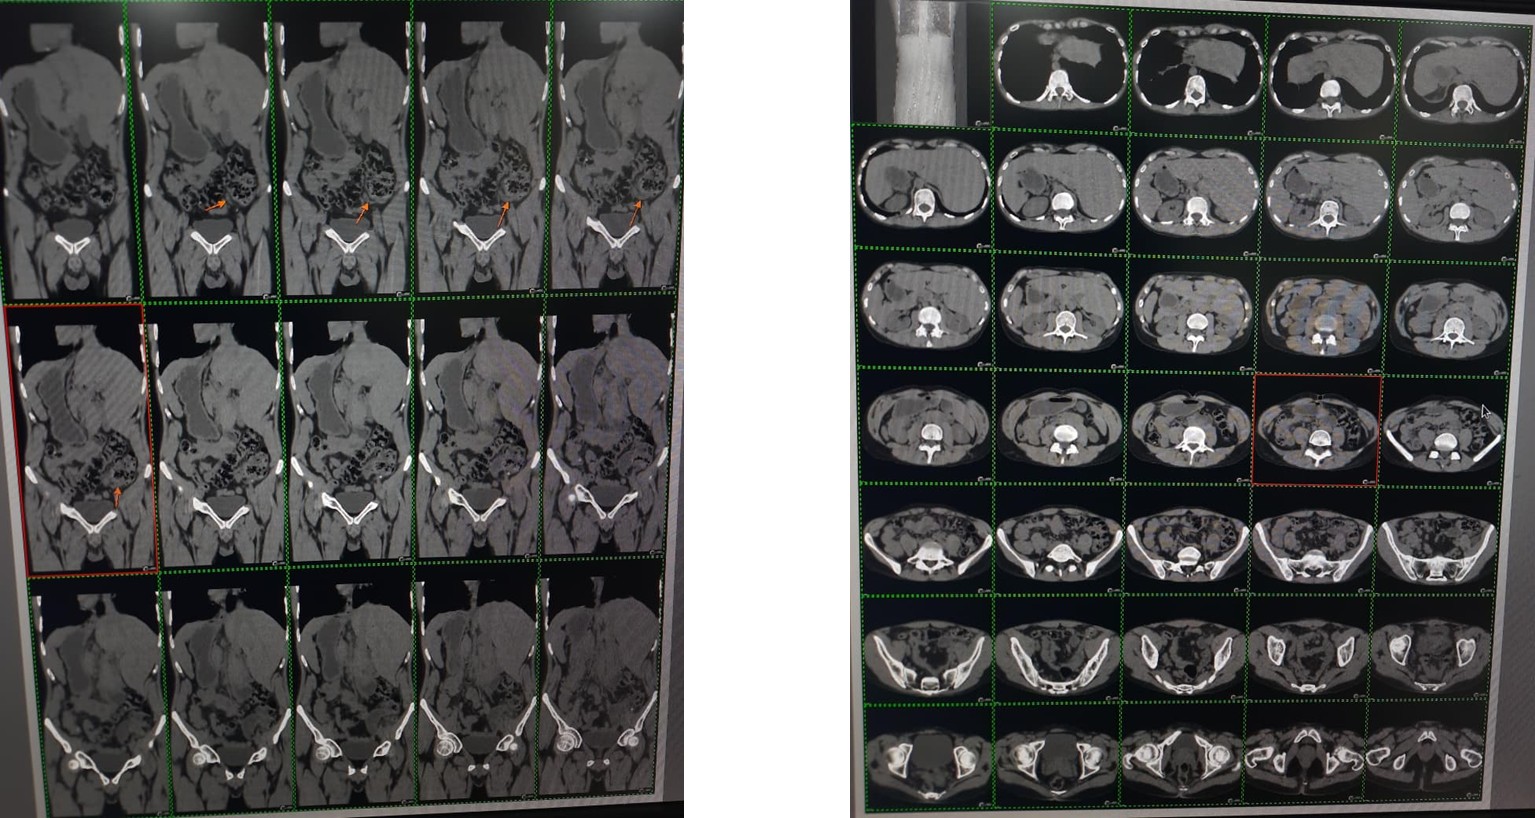

A 30-year-old male, presented with an unusual clinical history of pain in the left lower abdomen, initially mimicking diverticulitis or renal colic. However, further investigations revealed an unexpected diagnosis — situs inversus totalis, a mirror-image reversal of normal anatomy. Consequently, the appendix was located on the left side and was found to be inflamed.

The patient was diagnosed with acute appendicitis and required emergency surgical intervention. He had a significant past history of childhood COPD and was on regular medications, placing him at high risk for general anesthesia. In view of this, the anesthetist opted for laparoscopic appendicectomy under spinal anesthesia.

The surgeon prepared and started a surgery, made a small supra umbilical incision for 10mm telescopic post dis a diagnostic laparoscopy (every organ lay opposite to expectation). The liver glowed golden on the left, the spleen rested comfortably on the right side.

Situs inversus totalis is a fascinating example of human anatomical variation. Although it may be associated with certain health risks, many individuals with this condition live without significant complications. The diagnosis is typically established through imaging modalities such as X-rays, computed tomography (CT), or magnetic resonance imaging (MRI), which demonstrate the mirror-image positioning of internal organs. Awareness and understanding of situs inversus totalis are crucial for healthcare providers to ensure accurate diagnosis and appropriate management. However, this condition poses a significant challenge during clinical evaluation and surgical intervention, particularly in emergency settings.